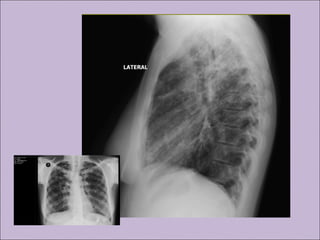

C) Anormalidades persistentes à radiografia de tórax

Manifestações sino-pulmonaresManifestações sino-pulmonares A)Colonização / infecção persistentes por patógenos típicos da FC como Staphylococcus aureus, Haemophilus influenzae, Pseudomonas aeruginosa e Burkholderia cepacia B) Tosse crônica e produtiva C) Anormalidades persistentes à radiografia de tórax D) Obstrução das vias aéreas E) Pólipos nasais, sinusite F) Baqueteamento digital Rosenstein. J Pediatr. 1998;132:389-95